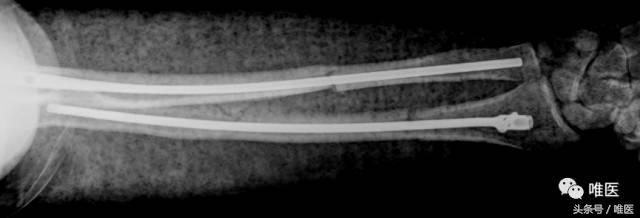

▣ 术后13月